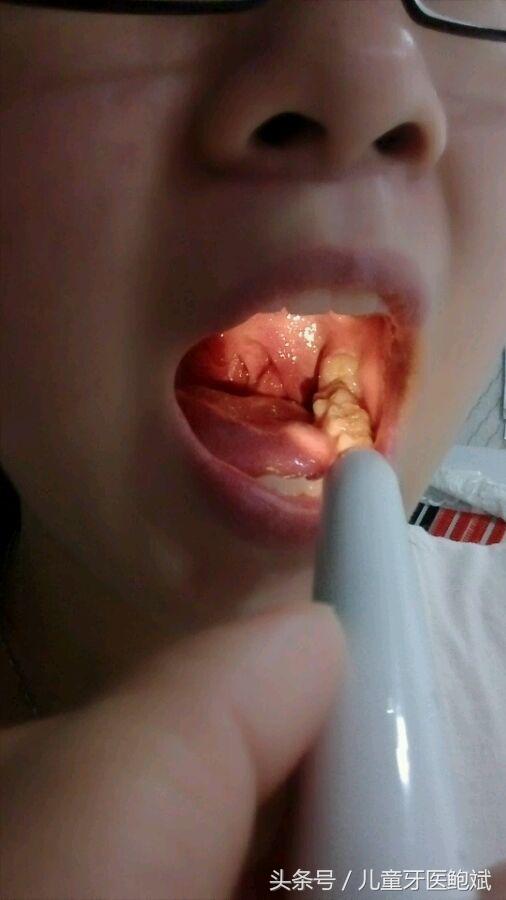

患者提问:鲍医生,我牙齿缝隙大,吃饭经常会塞牙,很多时候刷牙都刷不掉,牙签也不好使,像我这样牙缝大的平时怎么清洁口腔卫生好?

鲍医生:牙齿缝隙大,您可以使用牙线来配合刷牙清洁口腔卫生,牙签安全隐患大,建议尽量不要使用。相比口腔清洁的方法,您更应该到医院做一下牙齿检查,牙齿缝隙大,口腔不洁,容易发生牙周疾病和蛀牙,只有及时帮助牙缝闭合才是最好的办法,还能解决您塞牙的烦恼。

由于塞牙太常见,所以人们往往不会认为塞牙是什么大毛病,不引起重视。实际上,如果你经常塞牙,就应该去看看牙医。几乎所有的龋齿患者都发生过塞牙,其中有一种情况特别难受,就是龋齿发生两颗牙的邻接面,这里有一个龋洞,吃的东西都会塞进去。